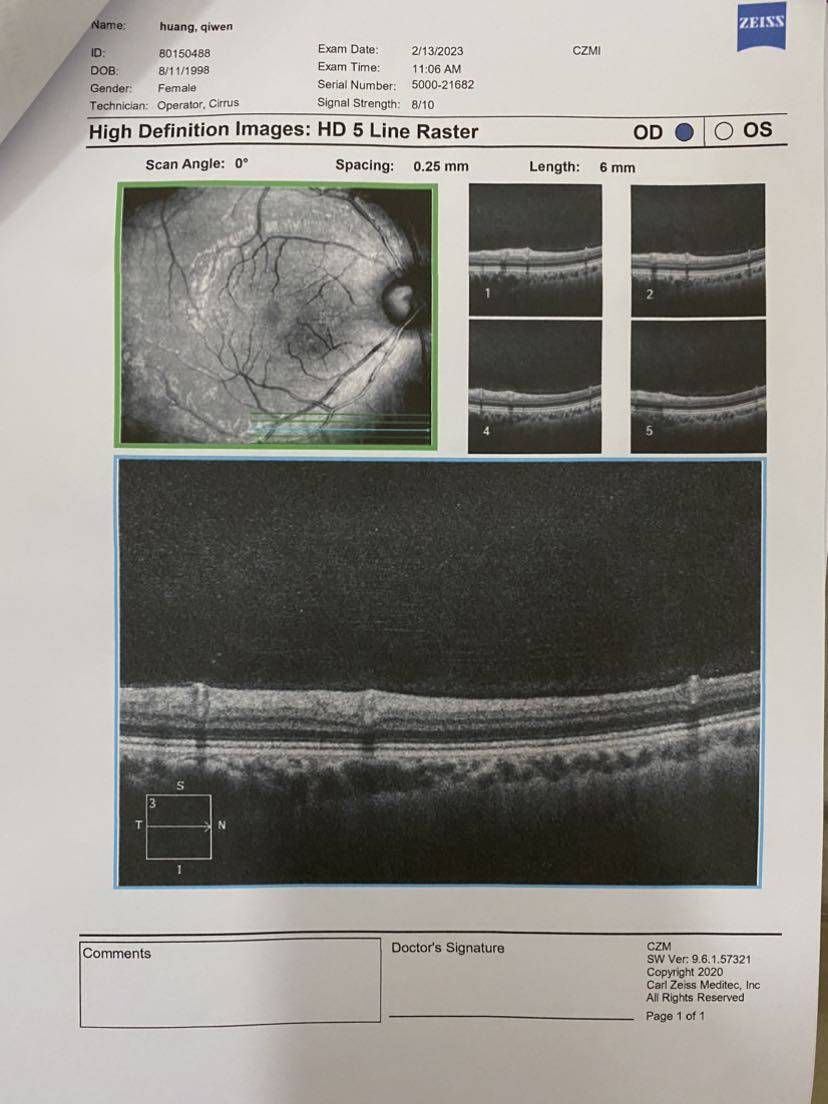

翻开第一页就说,视网膜很明显有问题。 说是什么前膜,说目前还没影响到黄斑(?),不影响视力,但如果后期发展拉扯到黄斑看东西就会变形……然后听不懂😂

说是什么前膜,说目前还没影响到黄斑(?),不影响视力,但如果后期发展拉扯到黄斑看东西就会变形……然后听不懂😂

说是什么前膜,说目前还没影响到黄斑(?),不影响视力,但如果后期发展拉扯到黄斑看东西就会变形……然后听不懂😂

说是什么前膜,说目前还没影响到黄斑(?),不影响视力,但如果后期发展拉扯到黄斑看东西就会变形……然后听不懂😂一开始挺凝重的,然后我说我有狼疮,医生好像就淡定了?!?

最后把所有报告记录一下,医生说要保管好。千万不能折,那就拍照先留个底吧~

【眼部ct】